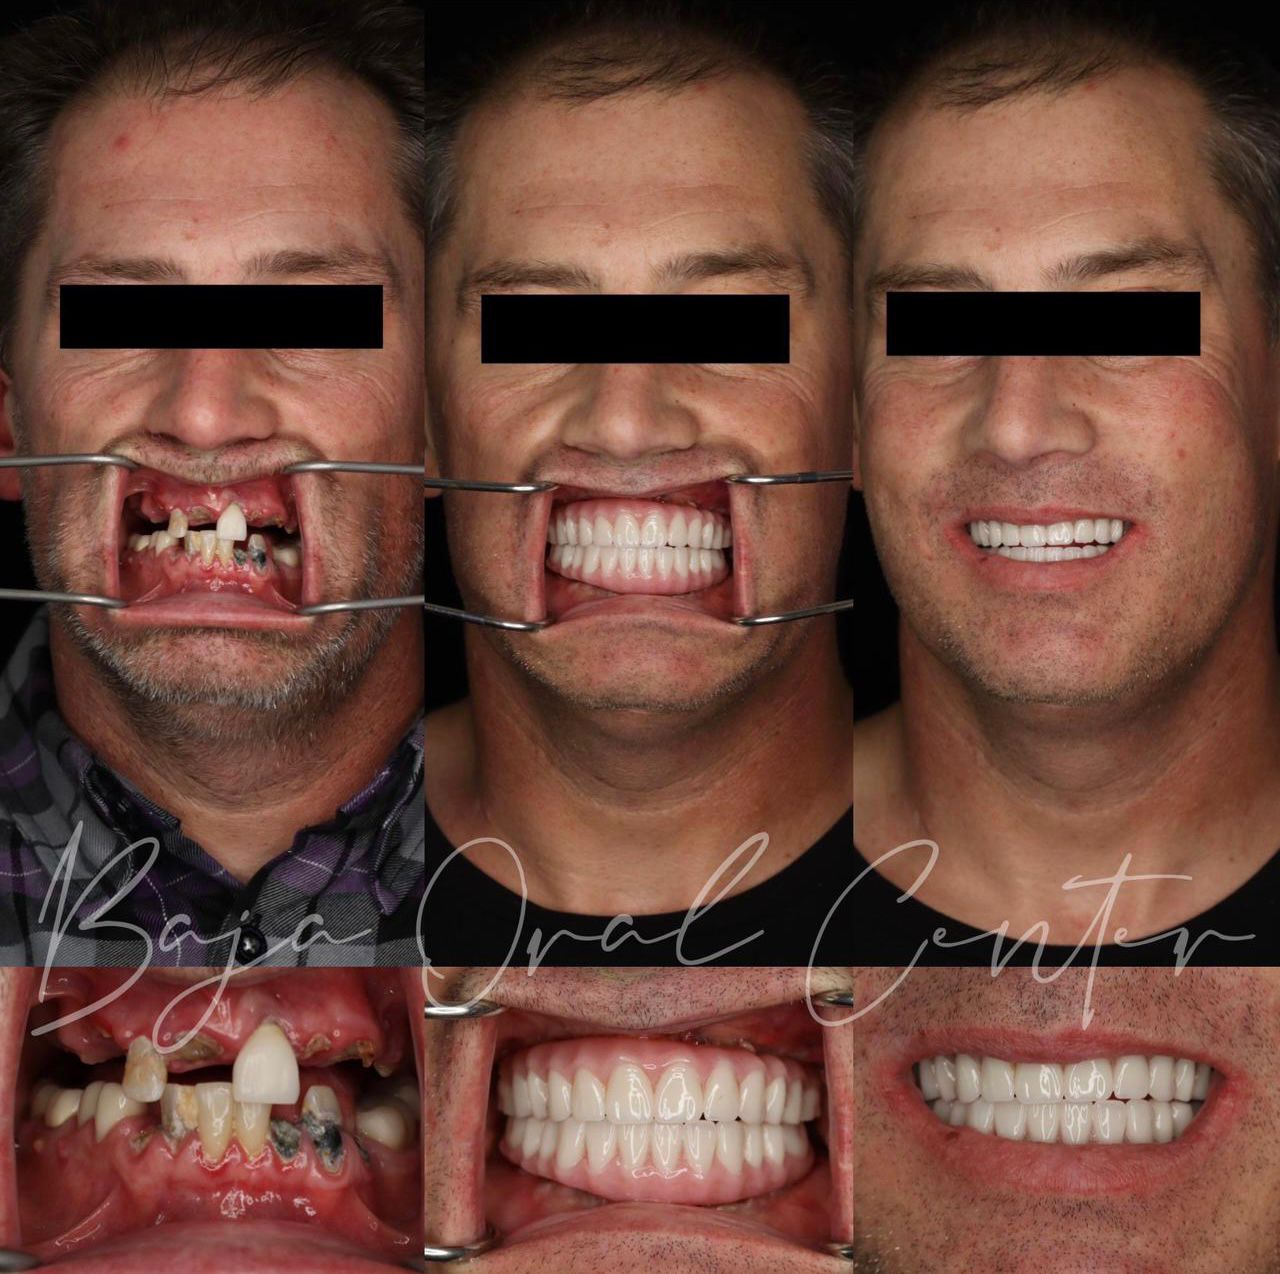

Start your smile transformation in just one trip to Tijuana. Your first phase includes extractions, 4 dental implants per arch, and fixed temporary teeth — all in one day. After 4–6 months of healing, you’ll return for your custom zirconia prosthesis for just $4,000.

Not all smiles need the same solution. That’s why we master every technique

All on 4

•All-on-4 or All-on-6 for stable, proven solutions when there’s an ideal jaw bone.

CORTICOBASAL technique

Phase 1: All on 4 — $7,850

What’s included?

✅ Complete diagnostics & personalized planning (CBCT + records)

✅ Expert placement of 4 implants

✅ Fixed temporary teeth in 72 hours so you can smile & eat right away

✅ Post-op medications & easy recovery support

Phase 2: all in 4 — $4,000

✅ Custom zirconia or premium hybrid final teeth for a perfect, natural look

✅ 5 Year warranty

We proudly showcase the positive experiences of patients who have undergone a full arch rehabilitation with traditional / Corticobasal Implants with Full Arch Baja